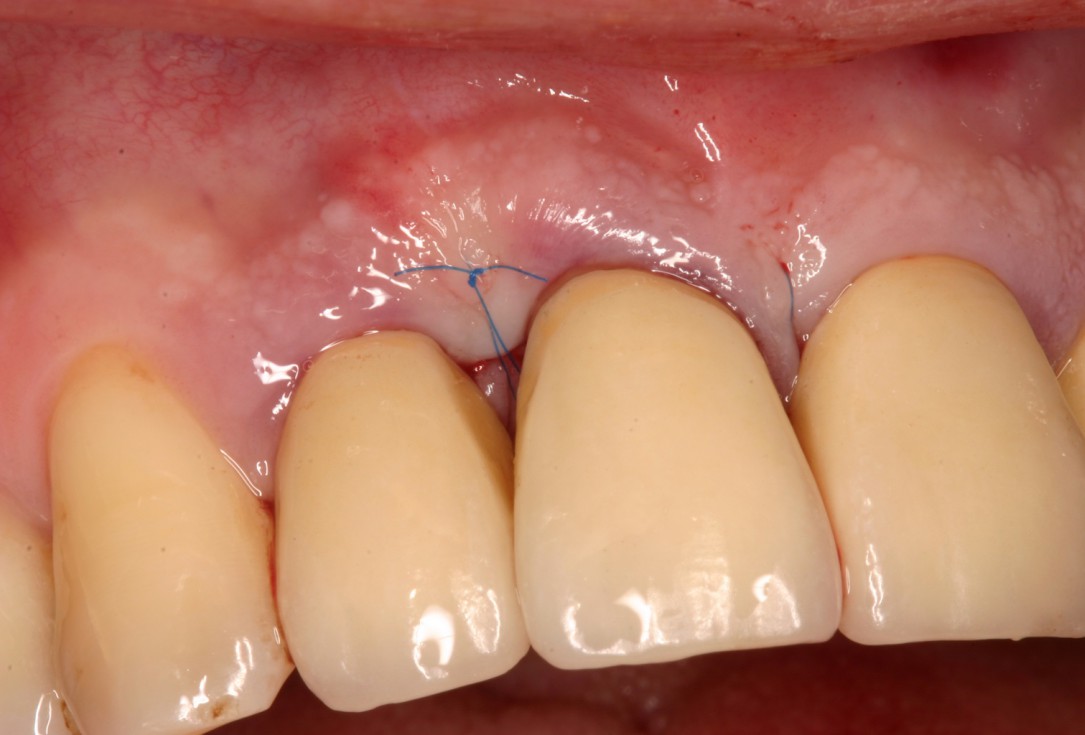

06/08 - Suturing to achieve complete wound closure.Non-contained intrabony defect treated with the simplified papilla preservation flap in conjunction with Straumann® Emdogain® and a particulate bone grafting material - Prof. Dr. Dr. A. Kasaj